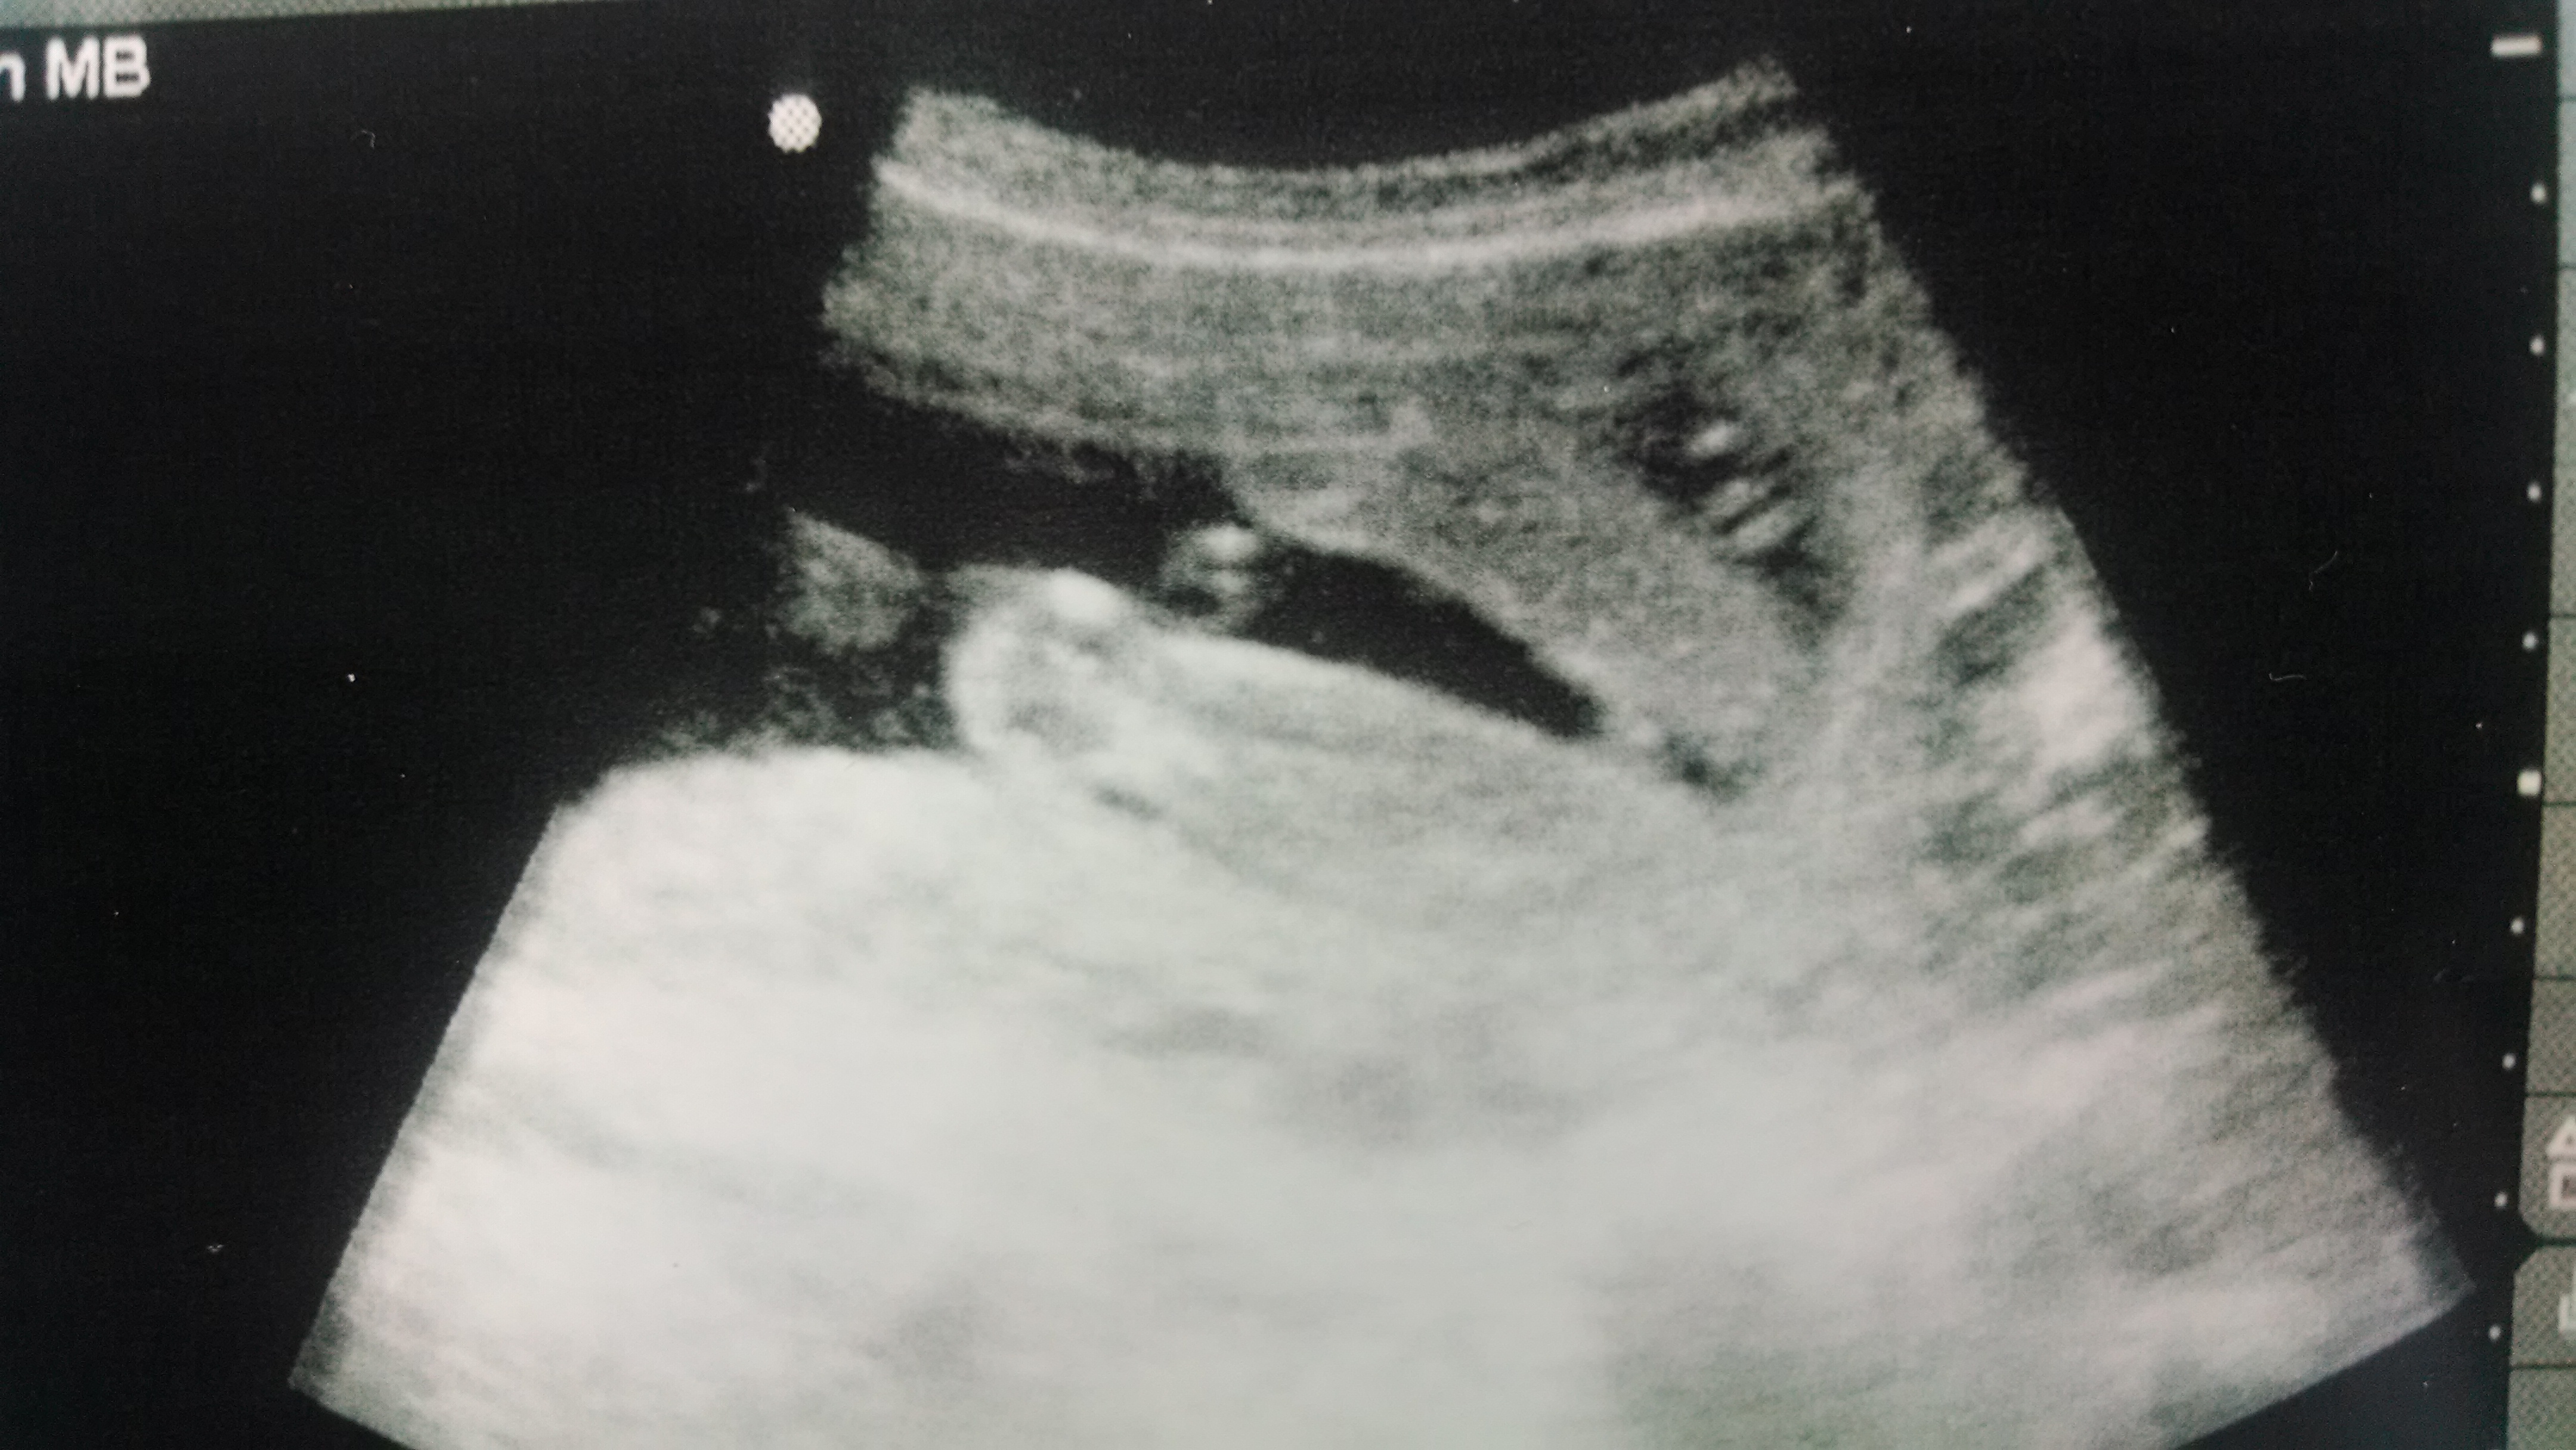

it is a girl..right?